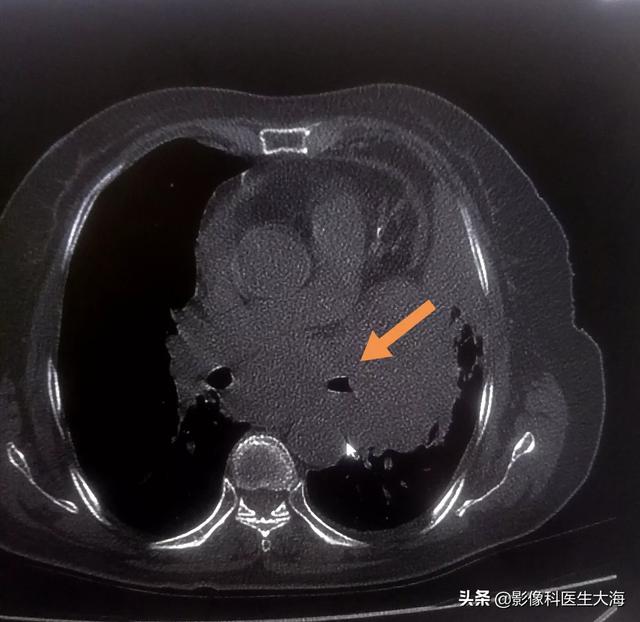

肺癌患者の嗄声が改善の兆しがなく徐々に悪化する場合は、基本的に腫瘍が反回喉頭神経を圧迫または侵害することが原因であることが確実であり、胸部強調CTと喉頭鏡検査を行って状態を明らかにすることができる。喉頭鏡検査で声帯の麻痺が認められれば、反回喉頭神経が障害されていることは確実です。反回喉頭神経が圧迫されているだけであれば、手術で切り離すことができますが、悪性腫瘍による反回喉頭神経浸潤では手術の可能性はほとんどありません。中心性肺がんによる反回喉頭神経の浸潤や縦隔リンパ節による反回喉頭神経の圧迫は、腫瘍が進行していることを意味します。

肺癌患者の声が以前は正常で明瞭で、病気の進行に伴って声がかすれるようになった場合、この時点では少なくともIII期、つまり末期である。嗄声が病的なものであれば、通常は縦隔リンパ節の転移によるもので、リンパ節が成長すると隣接する反回喉頭神経に浸潤し、この反回喉頭神経の浸潤によって同側の声帯が麻痺し、声帯の麻痺によって嗄声が生じます。肺がんの病期分類では、これは少なくともN2、通常は少なくともIIIBかIIICで、比較的晩期です。また、一部の肺癌患者が標的治療薬を使用した場合、嗄声の副作用が出ることがありますが、この副作用の割合は非常に低くなっています。

肺がんの腫瘤が反回喉頭神経を直接圧迫したり、肺がんが縦隔リンパ節に転移して反回喉頭神経を圧迫したりすることで、声帯の麻痺が起こり、嗄声が起こる。

中枢性肺癌では、嗄声の発生率が40%以上と高く、肺腫瘍が反回喉頭神経に直接浸潤する場合と、転移性縦隔リンパ節腫大により反回喉頭神経が圧迫される場合があります。なぜ喉頭神経の圧迫が嗄声の原因になるのでしょうか?